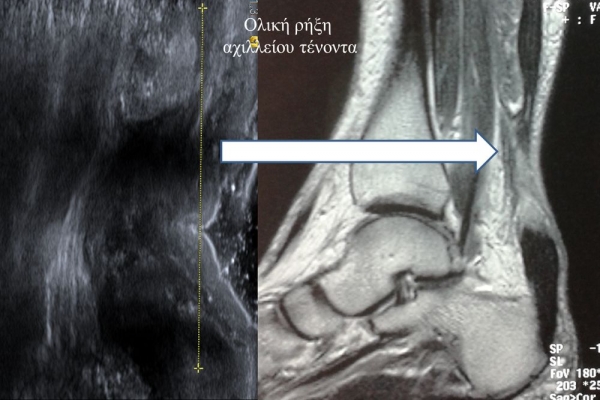

Πρόκειται για υπερηχογράφημα υψηλής ευκρίνειας που επιτρέπει την λεπτομερέστατη απεικόνιση (σε επίπεδο χιλιοστού) ακόμη και πολύ μικρών/επιφανειακών ανατομικών δομών και απαιτεί ειδικό υπερηχογραφικό εξοπλισμό καθώς και εξειδίκευση του ακτινολόγου. Η εξέταση γίνεται με δυναμικό τρόπο, δηλ εκτελούνται δοκιμασίες κίνησης του μέλους που πάσχει, ώστε να αποκαλυφθεί η παθολογίαακόμη και όταν δεν είναι εμφανής σε θέση ηρεμίας. Επιπλέον, η εξέταση είναι ανώδυνη και ασφαλής και δεν περιλαμβάνει ακτινοβολία (CT), μαγνητικό πεδίο (MRI) ή παραμονή σε κλειστό χώρο και είναι πολύ ανεκτή τόσο σε ενήλικες όσο και σε παιδιά.

- Ακρου Ποδός/ Πέλματος (πχ απονευρωσίτιδα)